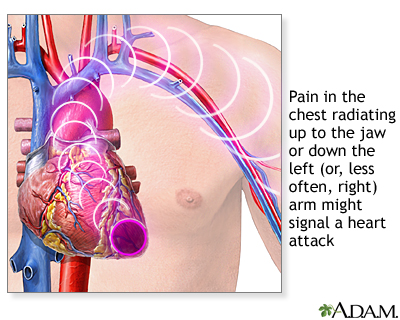

- Angina or a heart attack. The most common symptom is chest pain that may feel like tightness, heavy pressure, squeezing, or crushing pain. The pain may spread to the arm, shoulder, jaw, or back.

- Pain spreads (radiates) to your jaw, left arm, or between your shoulder blades.